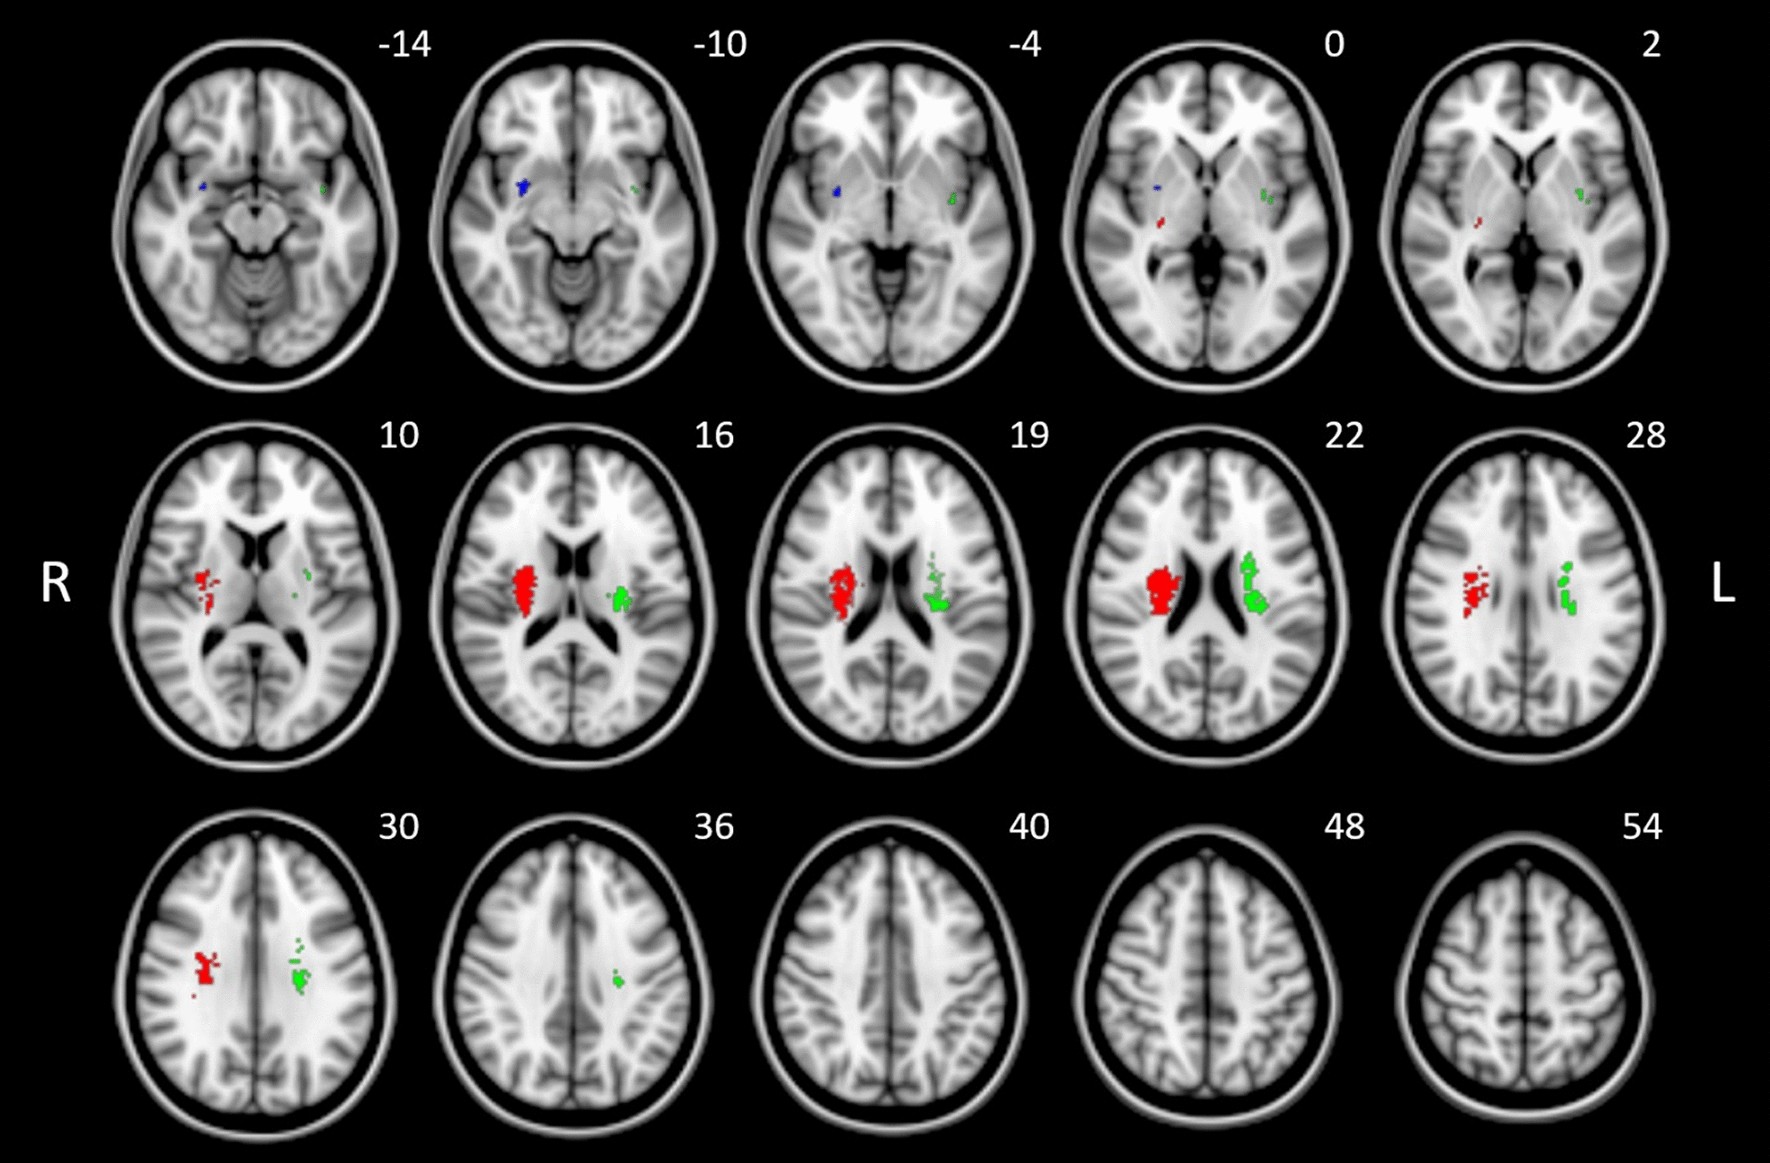

Figure 3

Results of SVR lesion-symptom mapping for the EQ-5D sum scores illustrated on a brain template in MNI standard space oriented in radiological convention. Three clusters with N > 50 significant voxels after permutation based on a threshold of p < 0.005 are shown. Clusters are color-coded to identify p-values after cluster-wise FWE correction (p = 0.036 [red]; p = 0.062 [green]; p = 0.298 [blue]). See also Table 1 for statistical and anatomical details. MNI coordinates of each transverse section (z axis) are shown.